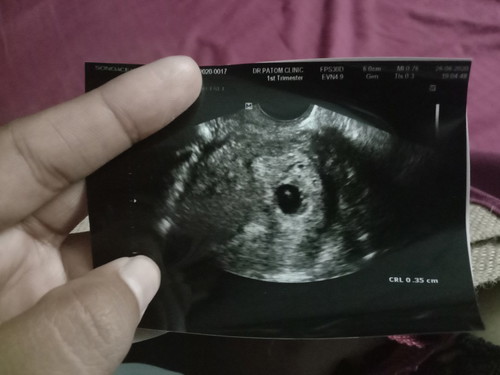

เลือดออกและมีลักษณะตกมาเป็นลิ่มเลือดไปซาวดูไม่พบถุงตั้งครรภ์ จนมาหมอคนสุดท้ายนี้ ตรวจpvให้จึงเห็นถุง แต่หมอบอกว่าถุงตั้งครรภ์ไม่สวย ถุงอยู่ต่ำมากรอหลุดออก แต่พอไปอีกคนบอกให้รอดู2 อาทิตย์ อาจเห็นน้อง แต่ถ้าไม่ก็แสดงว่าน้องไม่มีแล้ว อยากสอบถามว่ามีโอกาสที่น้องจะอยู่จิงๆไหมคะ